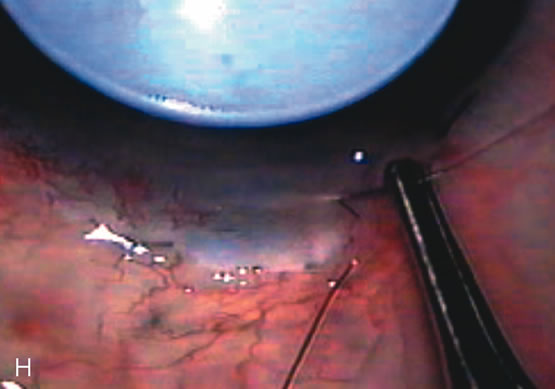

Trabeculectomy Construct the scleral flap, enlarge the wound and insert the IOL (Fig. 17). Instill miochol into the anterior chamber to achieve miosis. Remove the trabecular block and accomplish the peripheral iridectomy (Fig. 18). Some surgeons feel iridectomy may not be necessary;189 however, patients with increased inflammation due to intraoperative complications, uveitis, diabetes, neovascularization, or at increased risk for pupil block require iridectomy.

Close the scleral flap and titrate flow (Fig. 20). There are a variety of techniques to gauge flow through the flap. The punch technique is simple especially when used in conjunction with a scleral tunnel. Extend the punch to the end of the tunnel and excise tissue. This functions similar to a valve effect and only one or two sutures are needed to close the flap. Some surgeons prefer an adjustable releasable suture for this step. It is slightly more difficult to titrate flow with this technique.190 If both sides of the scleral flap are opened and a block removed, the valve-like effect is lost and more sutures are necessary to close the flap. This requires more effort and increased surgical time but increases the ability to titrate flow postoperatively.